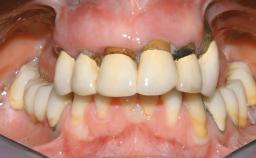

Immediate Loading of Six Implants in the Maxilla and Final Restoration with a Full-Arch CAD/CAM Zirconia FDP

A 63-year-old male patient was referred for a consultation and treatment of partial edentulism in the maxilla. The patient presented with residual anterior teeth and declined a partial removable prosthesis. He reported that the maxillary posterior teeth had been extracted due to mobility and periodontal disease two months before the consultation. The patient’s chief complaint was that his residual maxillary teeth were mobile and that he was unable to chew. The patient’s desire was a stable and comfortable fixed maxillary rehabilitation. The patient was a light smoker (fewer than 10 cigarettes/ day), and his medical history was without significant findings. He was not on any regular medication at the time of consultation. The extraoral examination revealed a normal physiognomy with a correct distribution of the facial thirds. The patient presented a low lip line, and the transition line between teeth and soft tissues was not exposed during a forced smile.

Prosthesis Type FDP

Defining Characteristics Fully edentulous upper jaw to be rehabilitated with an implant-borne fixed dental prosthesis

Loading Protocol Immediate

Retention Cemented, with prosthesis margin < 3mm submucosal Cemented, with prosthesis margin < 3mm submucosal

Provisional Implant-Supported Prosthesis Prosthodontic margin < 3 mm apical to mucosal crest Prosthodontic margin < 3 mm apical to mucosal crest